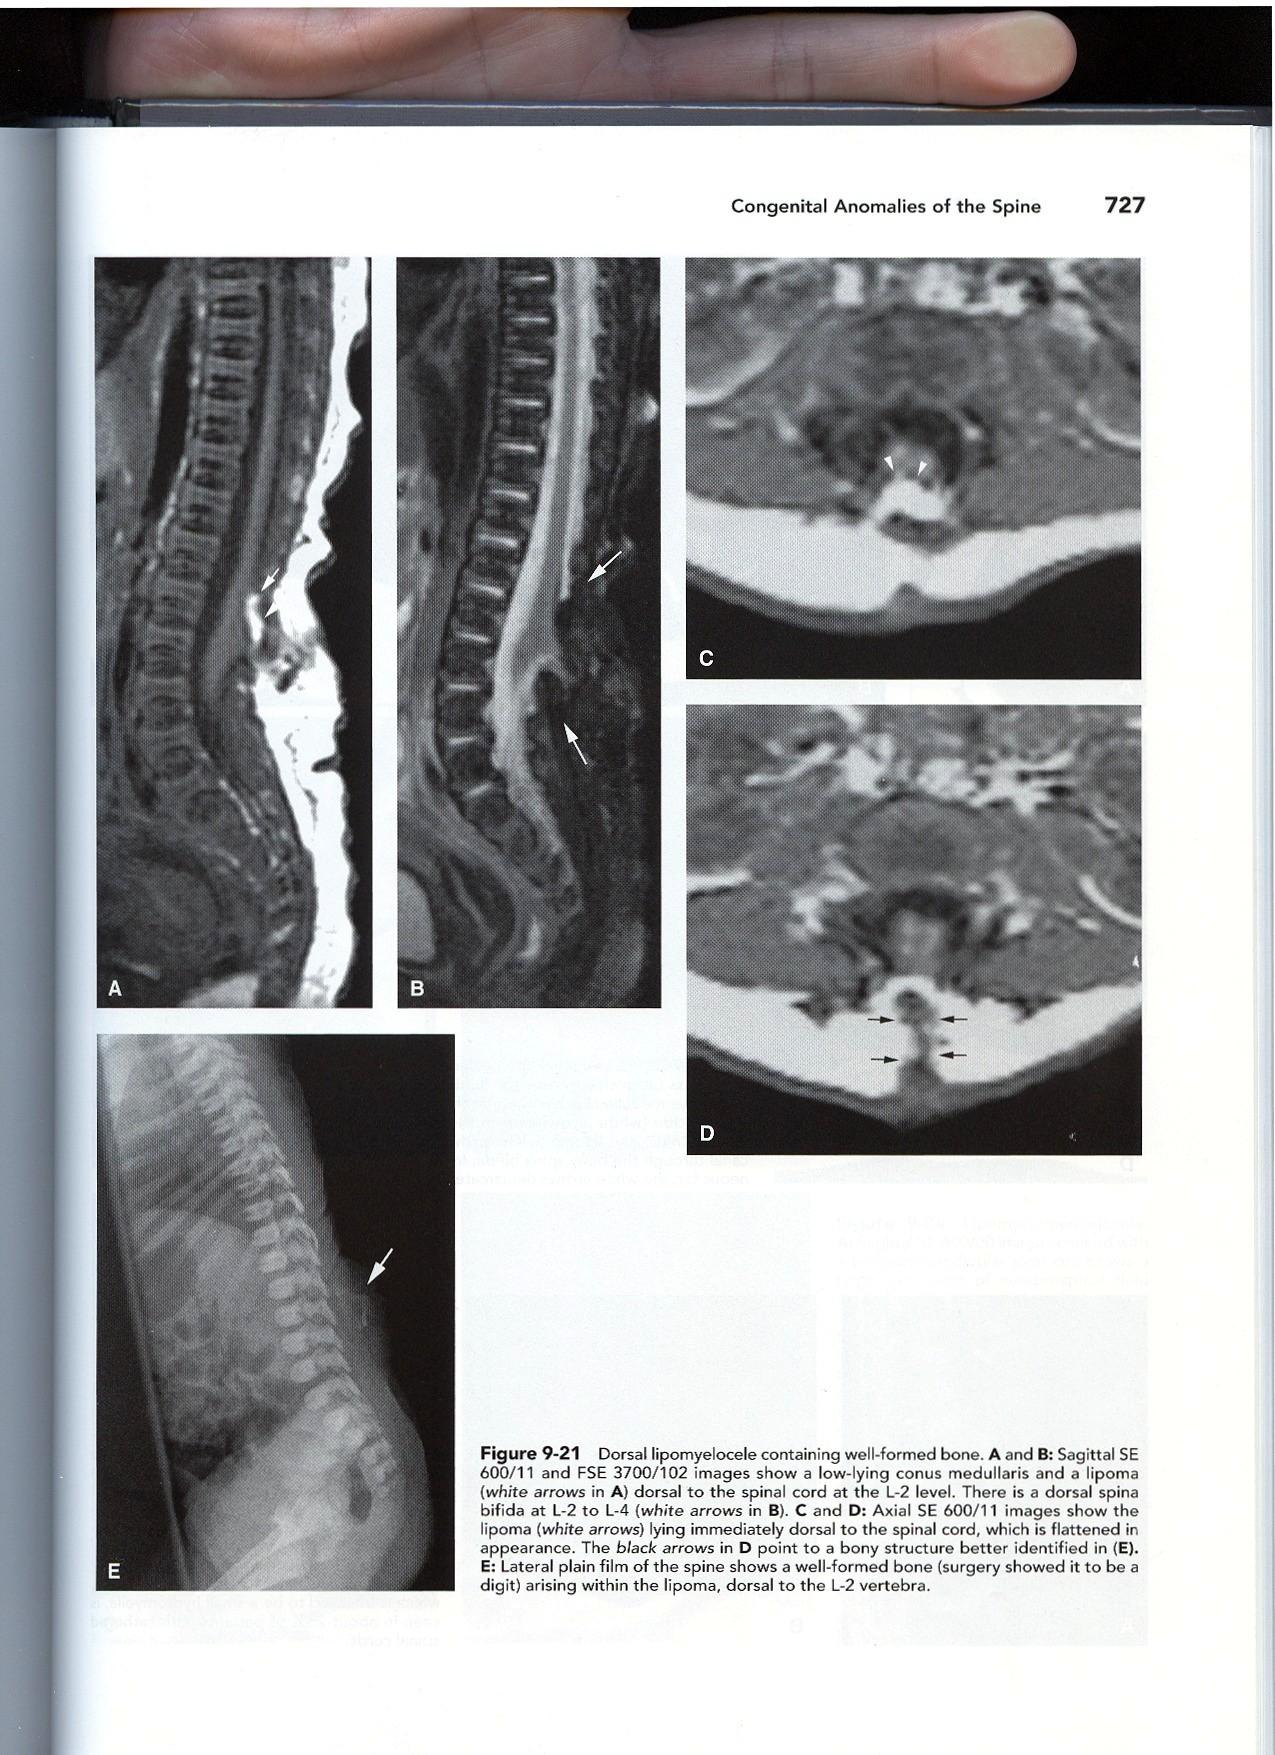

LIPOMA WITH DORSAL DEFECT

CSD WITH (OR W/O) SUB Q MASS

Lipomyelocele Lipomyelomeningocele

Key: The intrathecal fat associated with the low cord must be contiguous with the subcutaneous fat!

• “Lipoma with Dorsal Defect”

• Bony spine may or may not be intact

“LIPOMA

WITH DORSAL DEFECT”